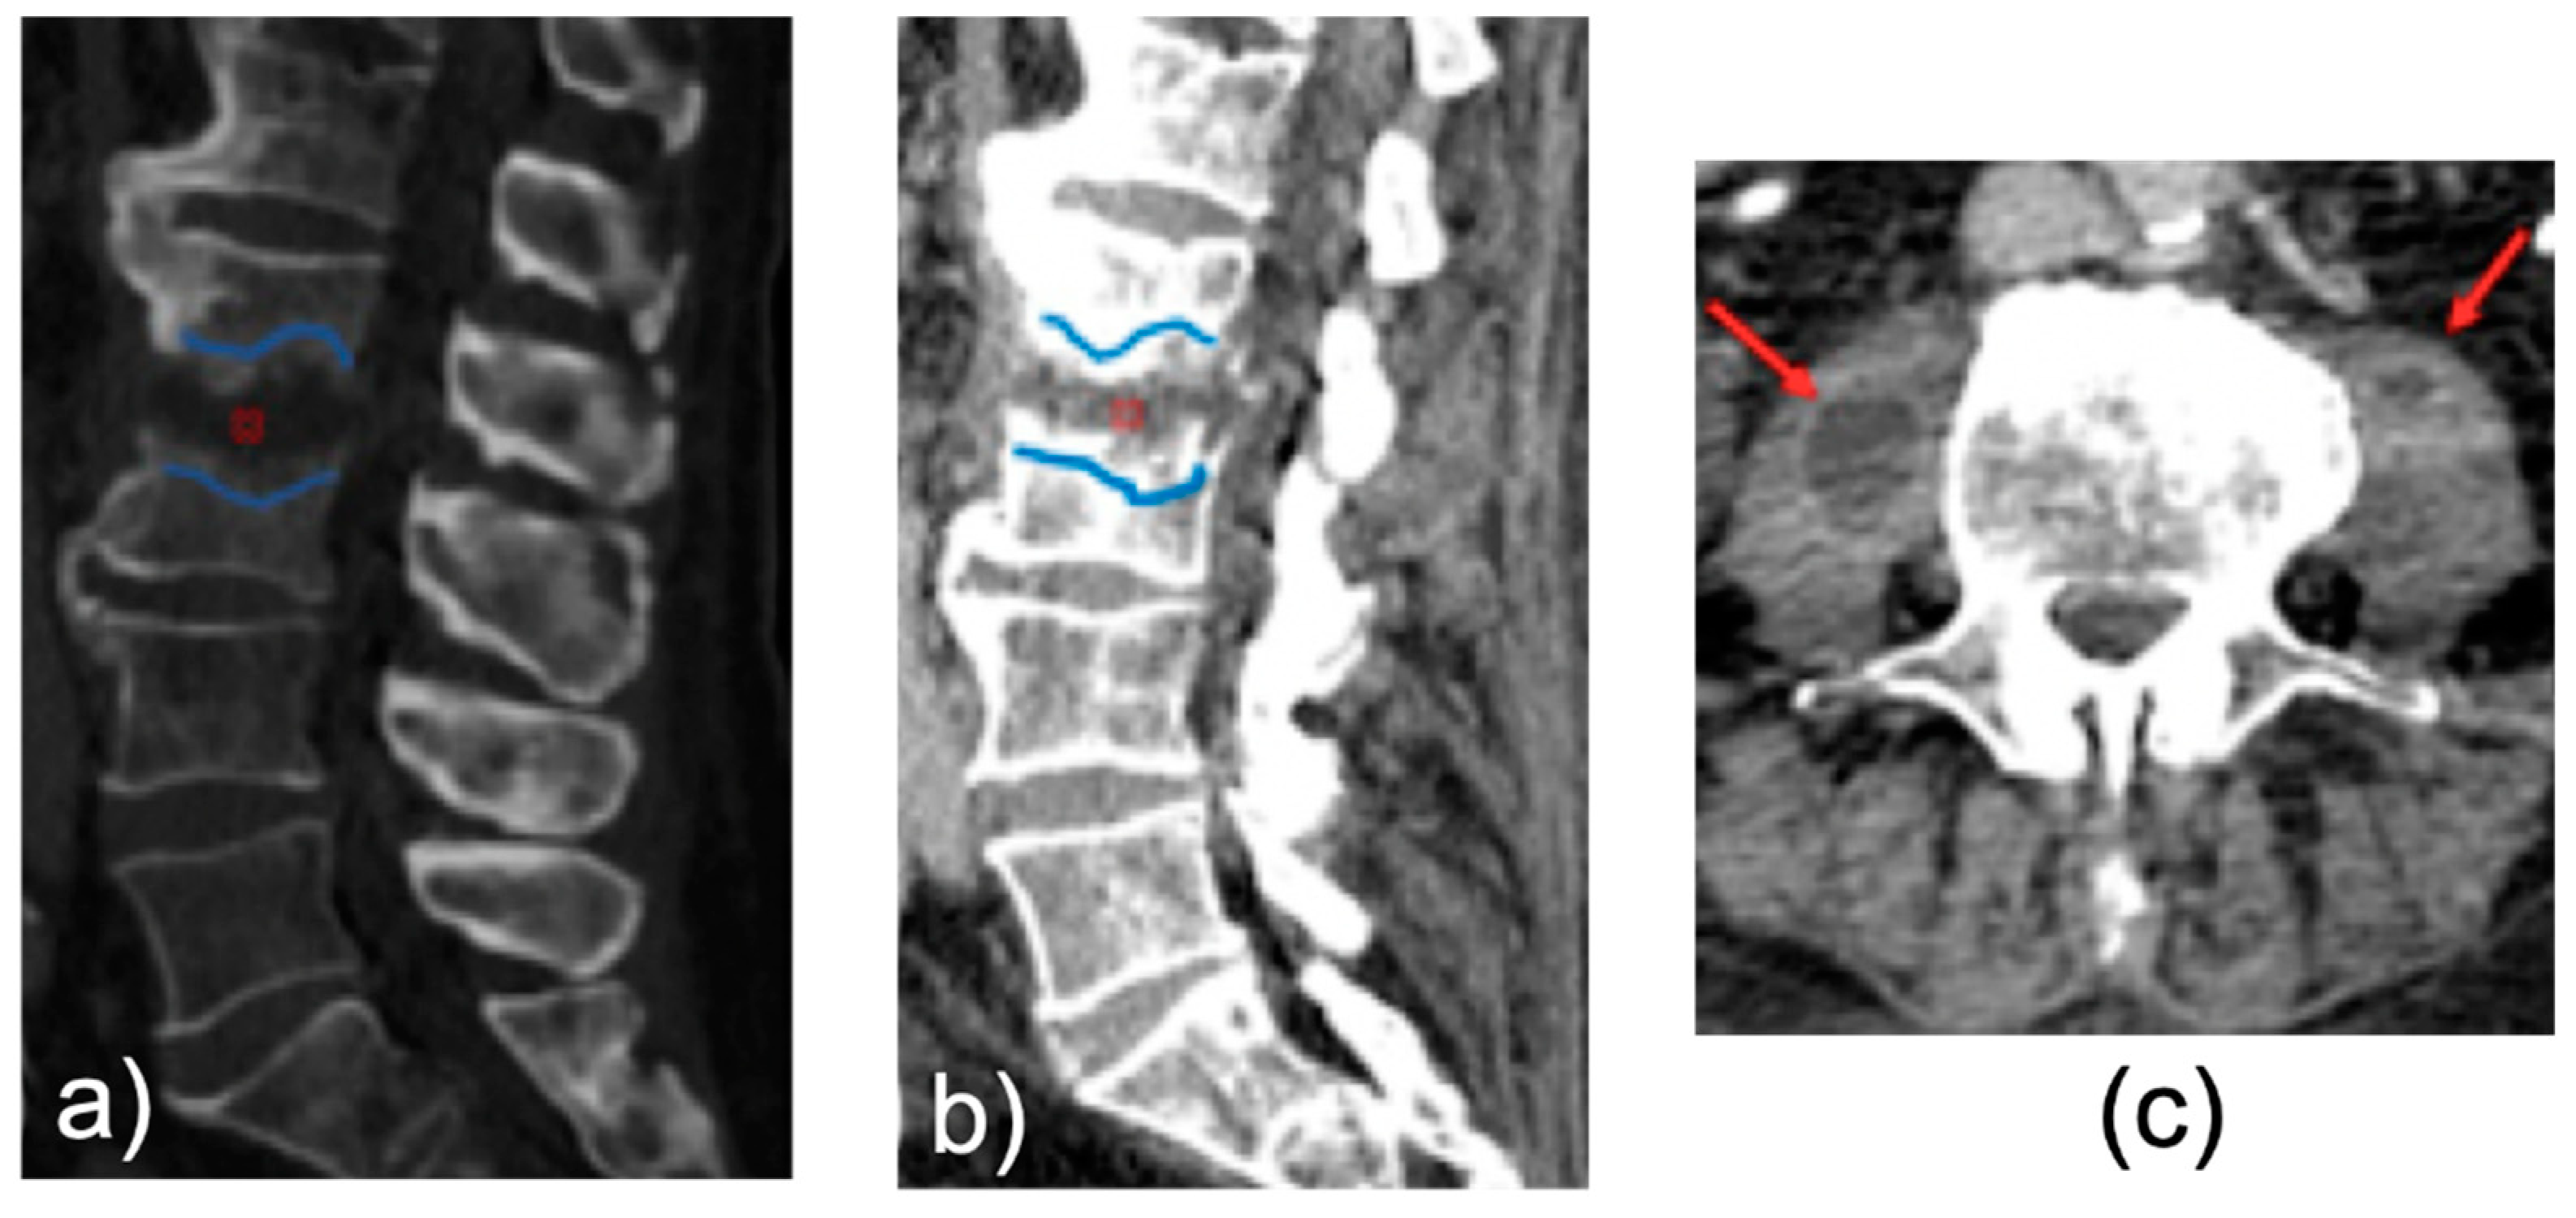

3. Results